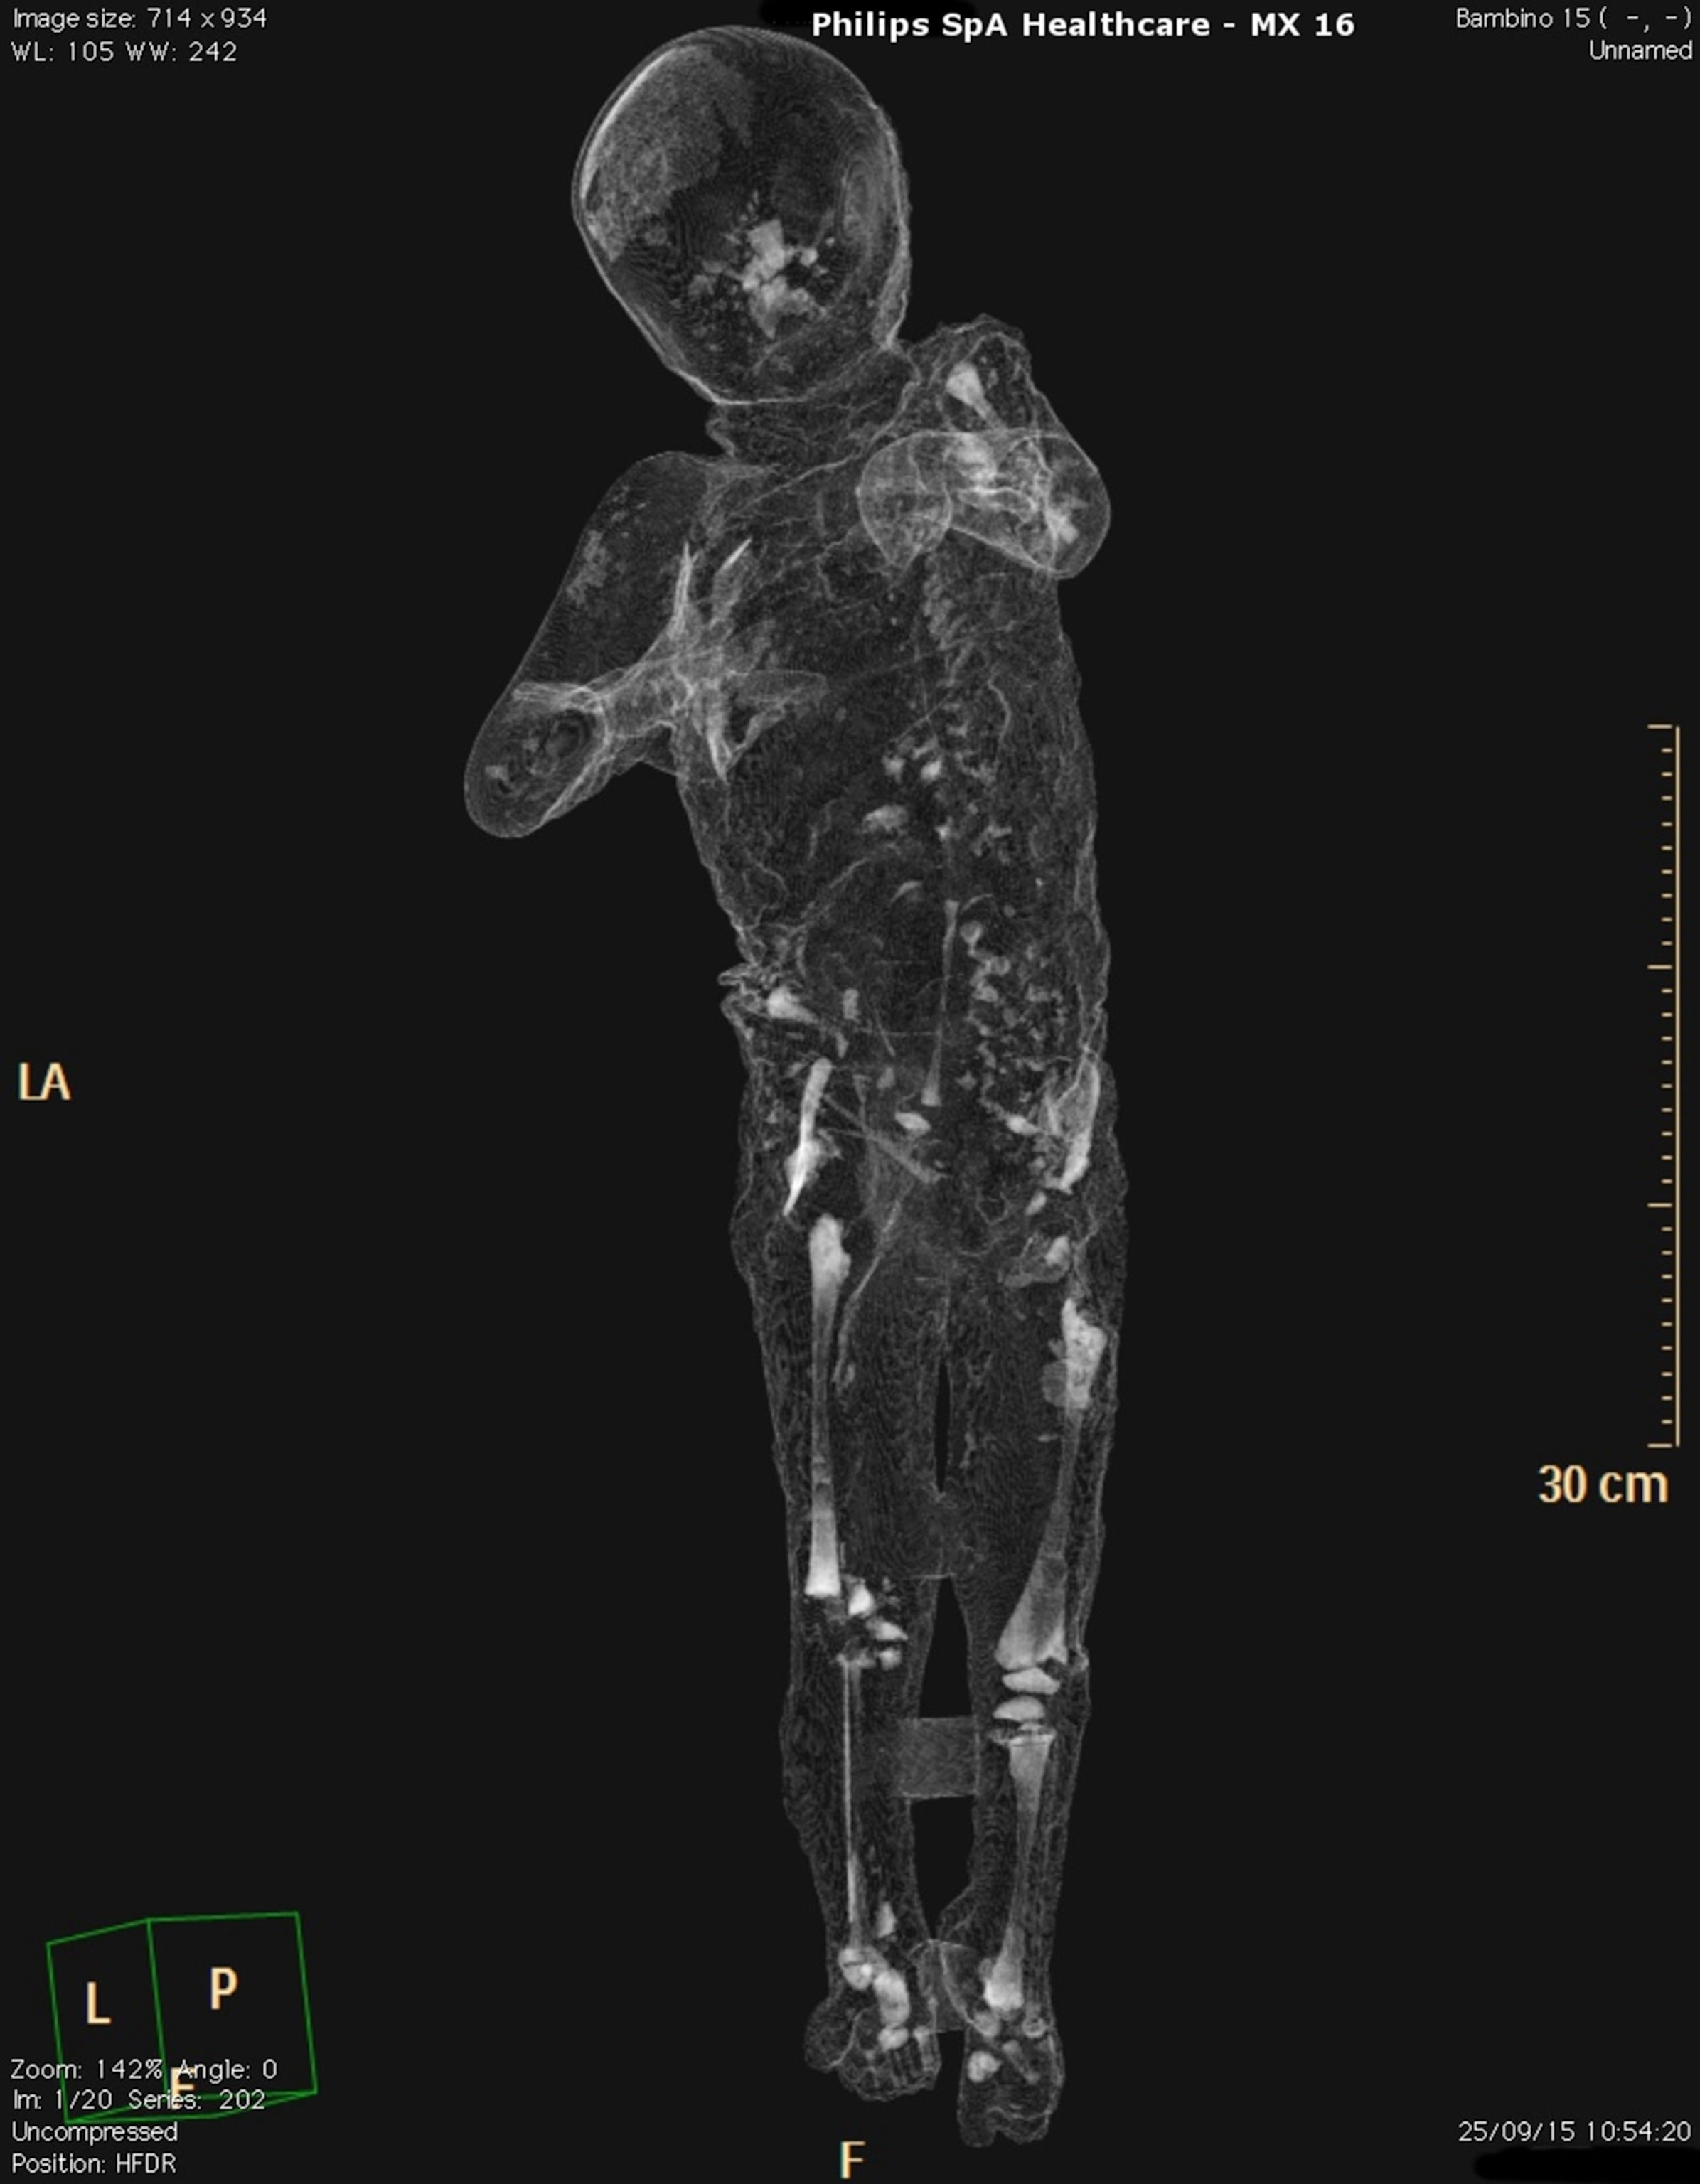

The project’s headline innovation has been the use of computerized axial tomography, popularly known as CAT scans, which employ radio waves and magnetic fields to generate detailed internal images of the body.

The procedure builds on earlier pioneering work by Giuseppe Fiorelli, Osanna’s most illustrious predecessor as superintendent (1863-1875), who injected high-quality plaster into the blocks of solidified ash that encased Pompeii’s dead, yielding evocative casts of their corpses. Some 86 of these casts and their human contents, a representative sample of the city’s population, are undergoing painstaking restoration and analyses, based on DNA samples and three-dimensional laser scans as well as tomography.

Like many of the project’s medical professionals, chief radiologist Giovanni Babino was surprised at his emotional response to the encounter with Pompeii’s dead. “I must say that I developed something close to a human relationship with these plaster images, sensations quite similar to those a physician experiences with actual patients.”

Teeth are the most resistant elements in the human organism, with qualities specific to each individual. Did the Pompeii deceased include musicians who played wind instruments? Were there carpenters, who clamped their jaws around nails before positioning them? The teeth will tell, say the project’s dental researchers, led by Dr. Elisa Vanacore of Salerno’s University Hospital. They can also help identify victims’ gender and age, suggest the region where they were born, and provide clues to their socio-economic class.